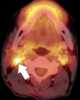

Necrotic lymph node metastasis

Lymphadenopathy or adenopathy is a disease of the lymph nodes, in which they are abnormal in size or consistency. Lymphadenopathy of an inflammatory type (the most common type) is lymphadenitis, producing swollen or enlarged lymph nodes. [Source: Wikipedia ]